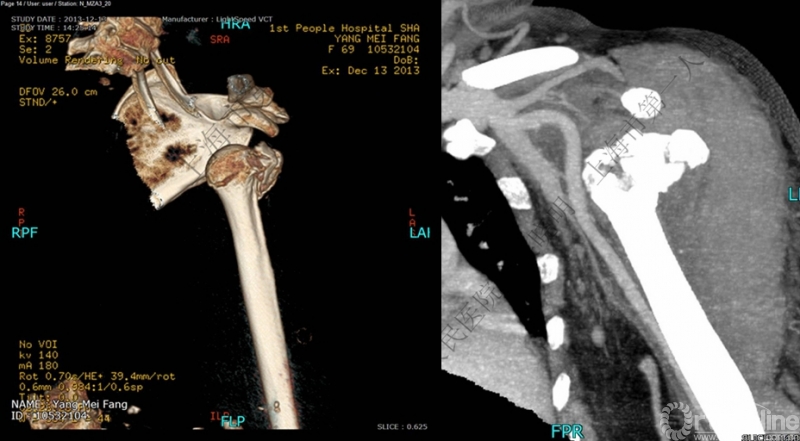

伴大结节骨折的老年性肩关节前脱位伴肱骨头外翻

肩关节前脱位合并大结节骨折&肱骨头外翻:外翻压缩型(Neer 分型)

对这型骨折进行手法复位会导致肱骨头和肱骨干之间的连续性消失。肱骨头和肱骨干之间连续性尚存,肱骨头前脱位(Robsion 3b)

外翻压缩型肱骨近端骨折

钢板固定

全麻下闭合复位,钢板固定